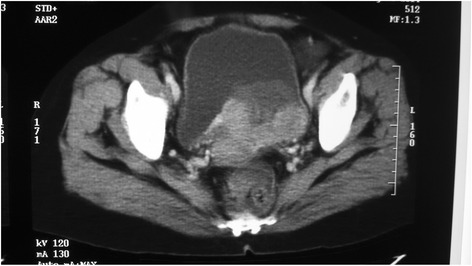

Eighteen months later, her routine follow-up US scan of KUB showed a mucosal lesion in the left base of the bladder which was confirmed by a CT scan (Fig. 1). It was confined to the bladder wall. She underwent transurethral resection of the bladder lesion which showed metastatic deposits of a high-grade papillary renal cell carcinoma (Figs. 2a and 2b). Immunohistochemistry showed strong membrane positivity for CD10 (Fig. 2c) while CK7 and CK20 were negative (Fig. 2d). Despite transurethral resection, the tumour was growing rapidly and she underwent total cystectomy and neobladder formation. Since then, she has interferon alpha injections thrice a week. Ten months after cystectomy, she developed a lung metastasis. She continues to have interferon and is well with an Eastern Cooperative Oncology Group (ECOG) performance status of 1, 6 months after the diagnosis of the lung metastasis.

Fig. 1.

CT scan showing a large irregular mucosal lesion in the left base of the bladder